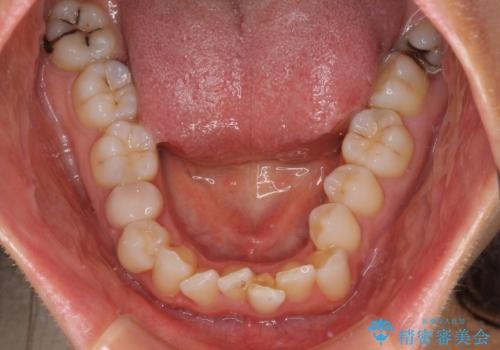

- 前歯のデコボコを気にして来院された患者様です。

IPR(歯と歯の間を削る)によってデコボコが解消するように設計し、インビザラインにより治療を行うこととしました。

下顎善の叢生をもう少し改善したかったのですが、患者様は十分に整ったとのことで治療を終えることになりました。